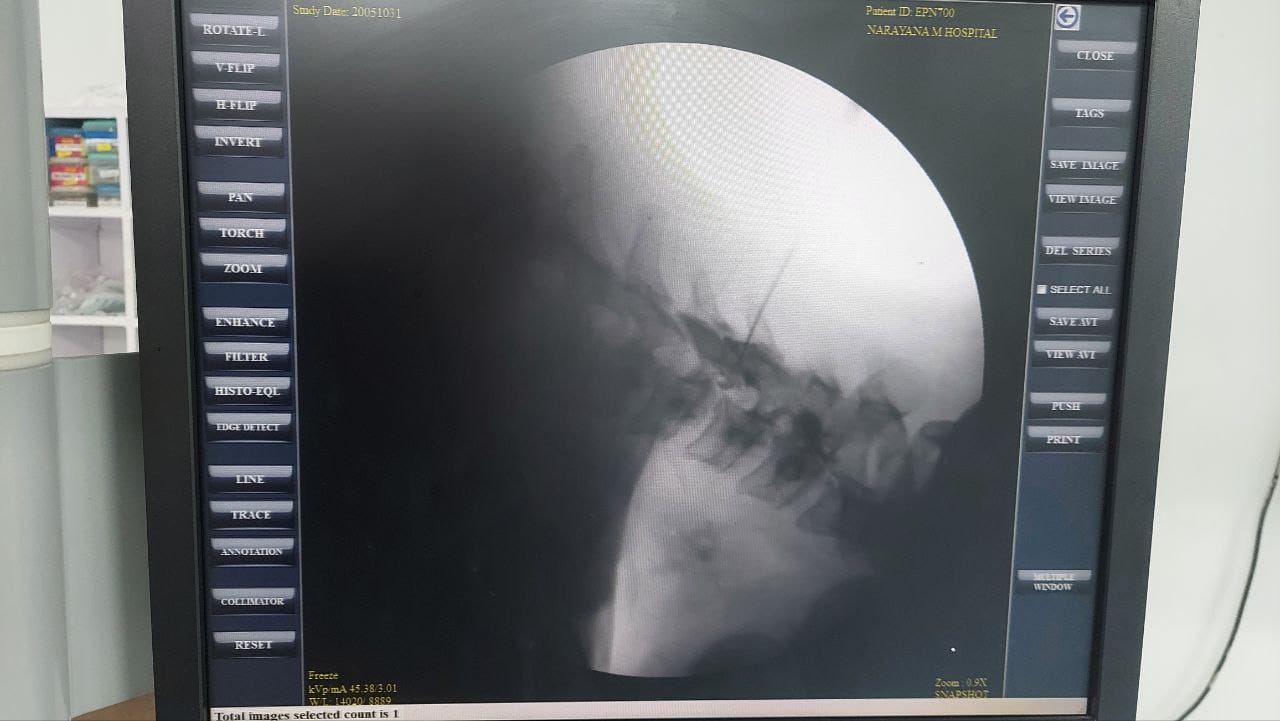

Procedures